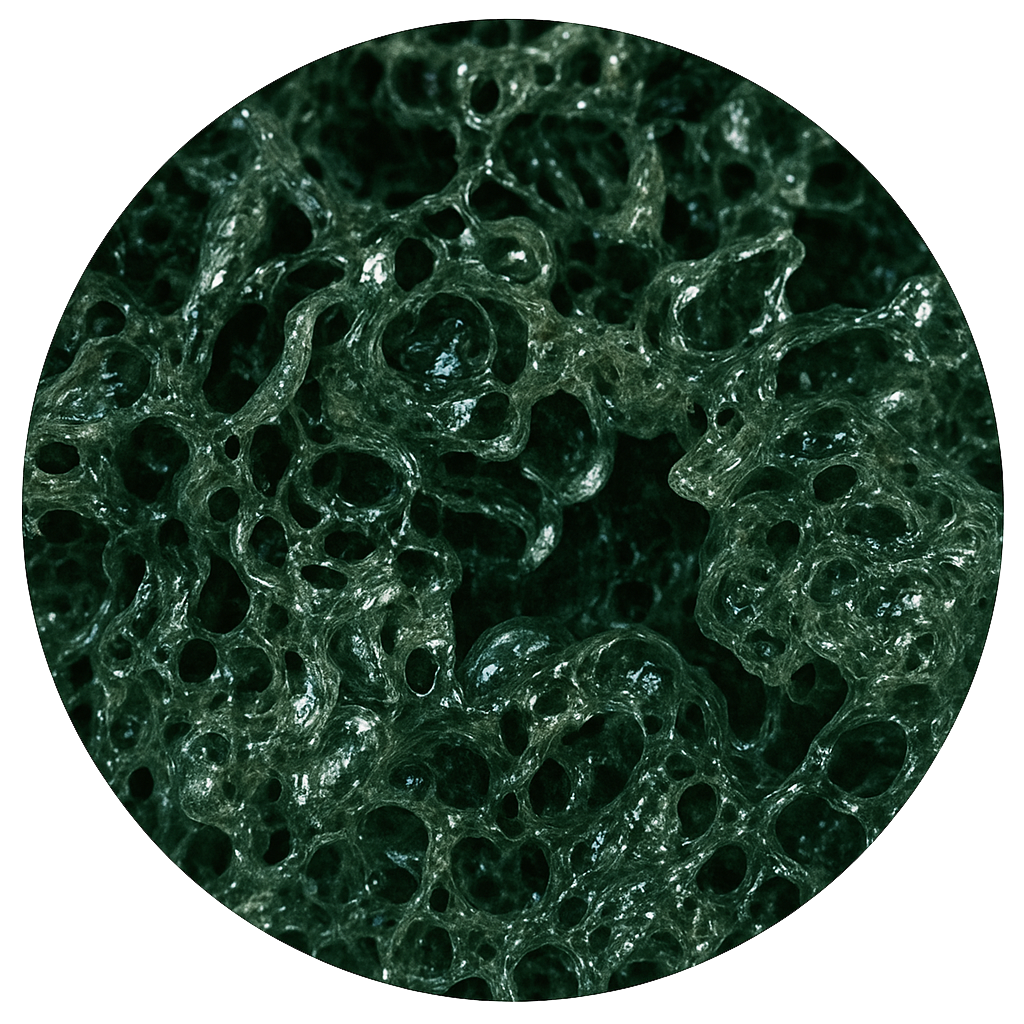

TRUE TEXTURE

Método propio de texturización con formación de poros abiertos en la membrana, sin utilizar impresión negativa, azúcar o cloruro sódico. Baja tasa de contractura capsular del 8,7% en 9 años.³ Otros fabricantes informan de tasas de hasta el 17% a los 10 años en el aumento primario⁴